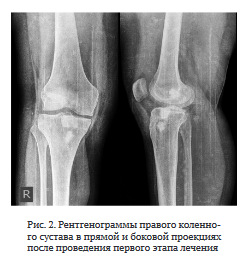

Первый этап лечения. Ревизия правого коленного сустава; удаление трансплантата ПКС; дебридмент;

УЗ кавитация раны; пластика дефектов костным цементом с ванкомицином (рис. 2). Результаты интраоперационного микробиологического исследования — МК8Е 103 КОЕ/мл. Интраоперационная кровопотеря составила 100 мл, гемотрансфузию не проводили. Рана зажила первичным натяжением. Дренаж удален на третьи сутки после операции.